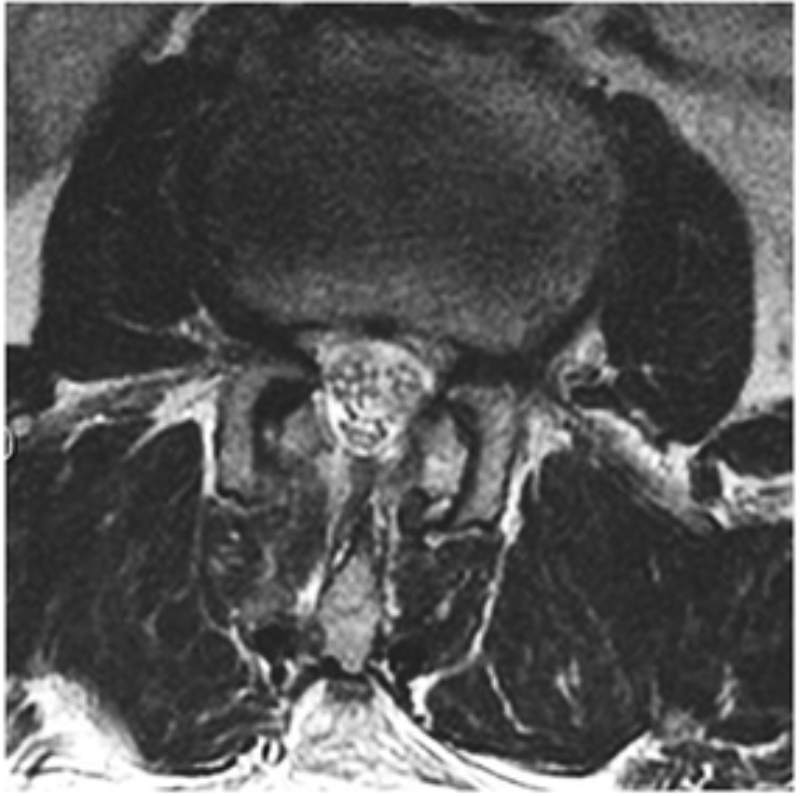

Slide the arrows to see what endoscopic spine surgery can do for your patient (L2-L3 Interlaminar Endoscopic Decompression)